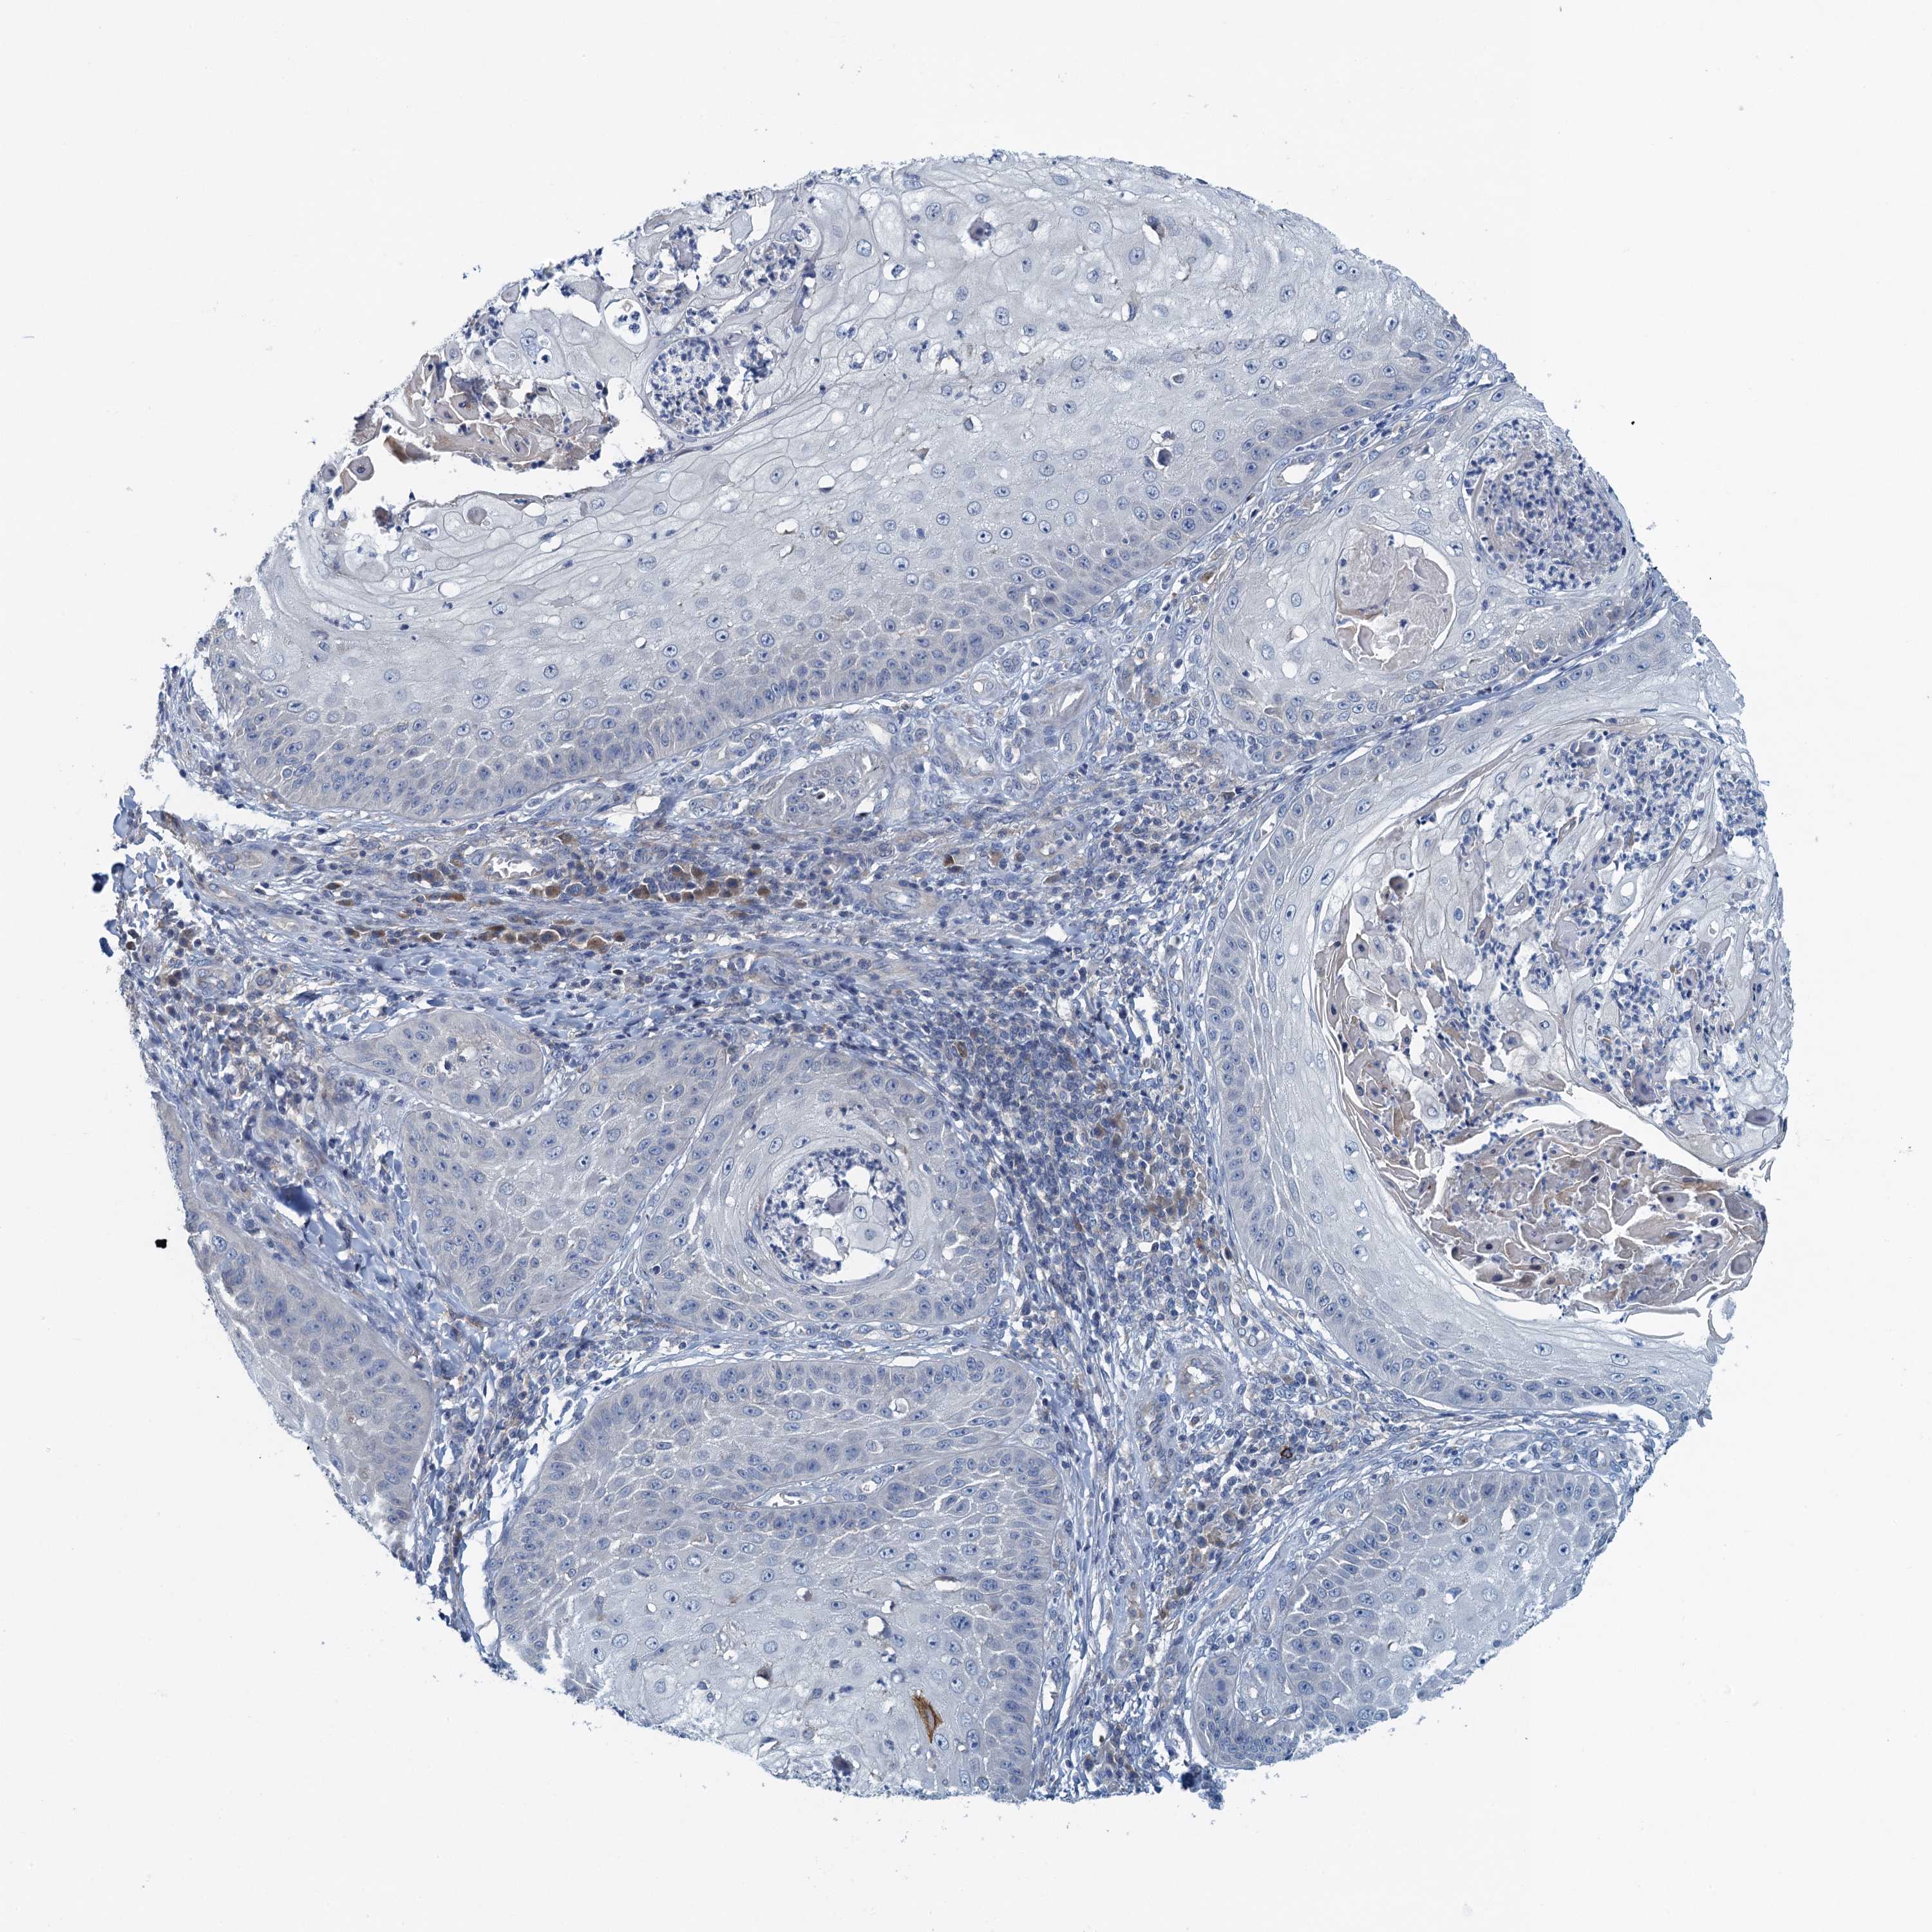

Basal cell and squamous cell cancer

SKIN CANCER - Protein expressioni

A mouse-over function shows sample information and annotation data. Click on an image to view it in a full screen mode. Samples can be filtered based on level of antibody staining by selecting one or several of the following categories: high, medium, low and not detected. The assay and annotation is described here.

Each image is clickable and will lead to virtual microscopy that enables deeper exploration of all samples and also displays staining intensity scores, fraction scores and subcellular localization as well as patient and tissue information for each sample.

Antibody HPA039490

Basal cell carcinoma